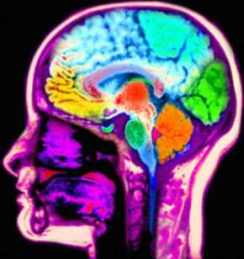

Los vídeojuegos violentos alteran el cerebro al punto que ese pernicioso efecto puede verse en las imágenes de resonancia magnética, señalan expertos que participan en la reunión anual de la Sociedad Radiológica de América del Norte.

En el grupo de los jugadores se observó menor actividad en el área frontal cerebrals escaneadas que afectan el funcionamiento del cerebro, con lo cual por primera vez se muestra en imágenes el efecto físico en el cerebro, con tan sólo una semana de juego.

Esa zona cerebral es importante en las funciones cognitivas y el control de las emociones y la conducta agresiva.